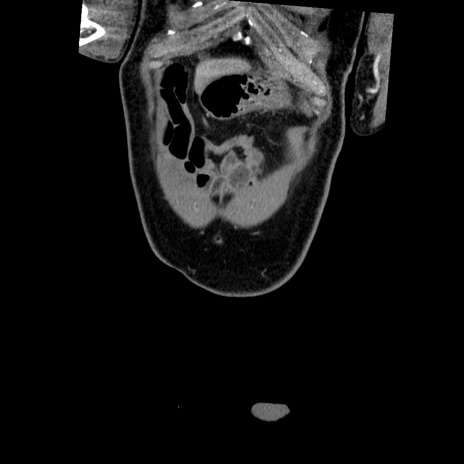

症例22(冠状断像)

【症例】50歳代男性

【主訴】腹痛

【現病歴】AVMからの被殻出血のため回復期リハ病棟入院中。 本日午後3時頃急に下腹部痛が出現した。

【既往歴】AVM、被殻出血、虫垂炎、高血圧

【身体所見】意識晴明、左半身不全麻痺、会話の理解は良好、36.5°C、腹部:膨隆、全体に板状硬、下腹部正中に圧痛点あり、反跳痛-、筋性防御不明、右下腹部にope scar

【データ】WBC 9400、CRP 0.06

横断像